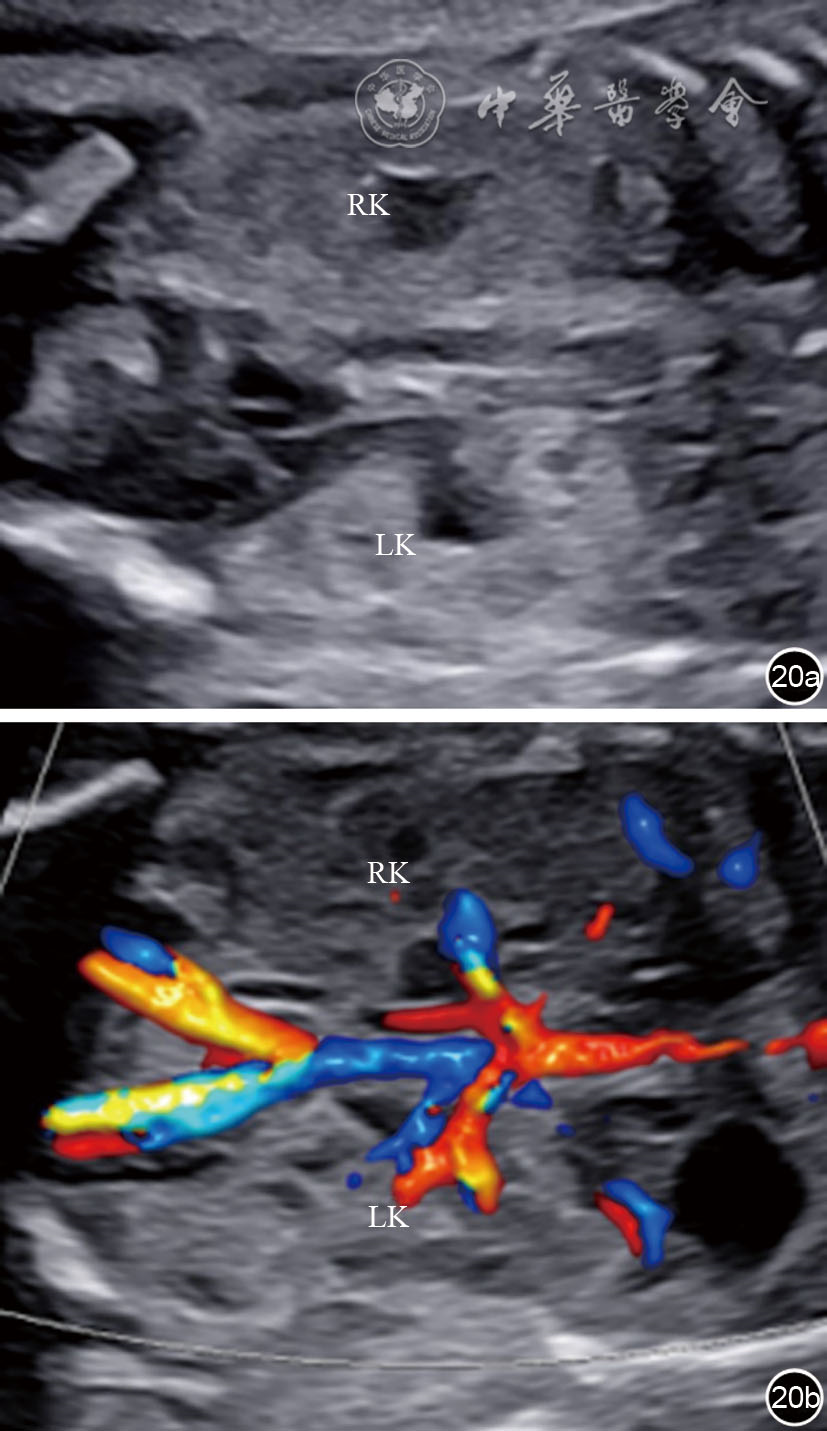

图20 双肾冠状切面超声图像及彩色多普勒血流成像(CDFI)。图a为双肾冠状切面;图b为双肾冠状切面CDFI 注:RK为右肾;LK为左肾